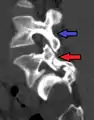

Retrolisthesis

Grade 1 retrolistheses of C3 on C4 and C4 on C5

A retrolisthesis is a posterior displacement of one vertebral body with respect to the subjacent vertebra to a degree less than a luxation (dislocation). Retrolistheses are most easily diagnosed on lateral x-ray views of the spine. Views, where care has been taken to expose for a true lateral view without any rotation, offer the best diagnostic quality.

Retrolistheses are found most prominently in the cervical and lumbar region, but can also be seen in the thoracic area.